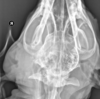

Review normal VD/DV anatomy.

A